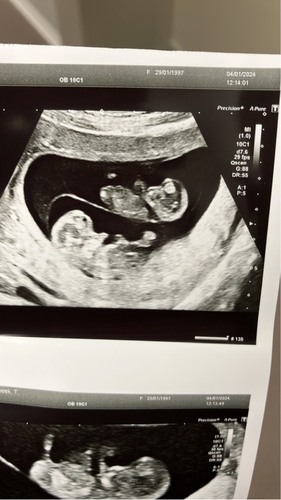

Ahhhh...ik 13+4 dinsdag hebben we 13w echo

Ah spannend鈽猴笍 ik 25januari de 13weken echo , voel je je goed?

Gisteren uitslag Nipt, alles in orde.